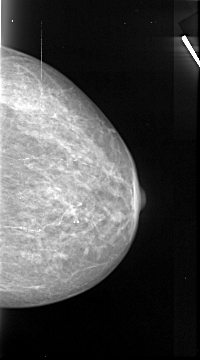

A_1071_1.LEFT_MLO

LEFT_CC LINES 4231 PIXELS_PER_LINE 2971 BITS_PER_PIXEL 16 RESOLUTION 42 OVERLAY

LEFT_MLO LINES 5296 PIXELS_PER_LINE 2881 BITS_PER_PIXEL 16 RESOLUTION 42 OVERLAY